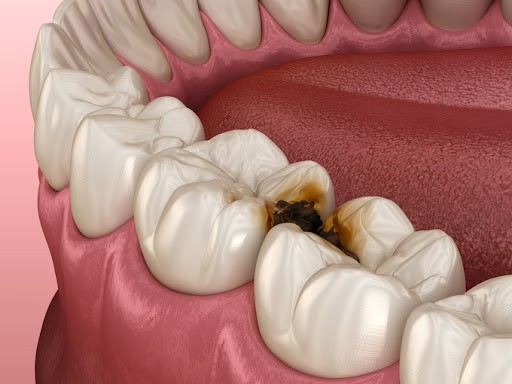

충치 치료

One Day 인레이 – 하루 만에 끝내는 충치 치료

충치 치료, 더 이상 미루거나 두려워하지 마세요.

직장‧학교‧가사로 바쁜 요즘, 2-3회 내원은 큰 부담이 됩니다.

플란트구강악안면외과 치과는 3D 디지털 스캔+설계+밀링 시스템으로 인레이 제작-부착을 당일에 완료해 시간을 확 줄였습니다.